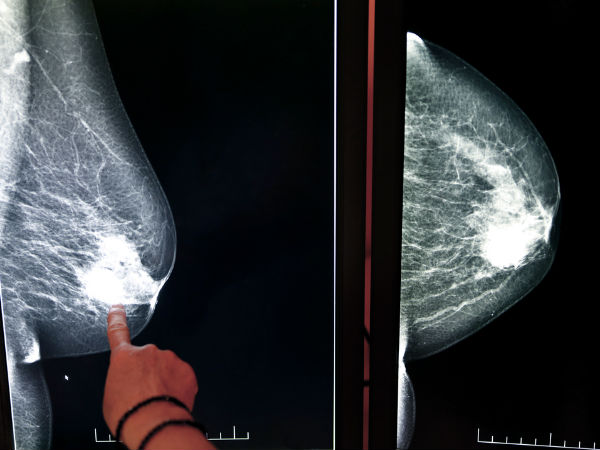

நைட் சிஃப்ட் போகும் பெண்ணா நீங்க? இந்த நோய்க்கான ஆபத்து!! எச்சரிக்கை!!

பெண்களை தாக்கும் ஆபத்தான நோய்களில் மார்பக புற்று நோயும் ஒன்று. அது எதனால் வருகிறது என புதிய காரணம் ஒன்றை ஆராய்ச்சி ஒன்று சொல்லியுள்ளது. அதனைப் பற்றி இங்கு காண்போம்.

மார்பக புற்று நோய் அறிகுறி:

உலக அளவில் பெண்கள் அதிகம் பேர் இந்த மார்பக புற்று நோயால் பாதிக்கப்படுகின்றனர். மார்பக திசுக்களில் உண்டாகும் கட்டி, மார்பக வடிவத்தில் ஏற்படும் மாற்றம், சருமத்தில் குழிகள் ஏற்படுவது, மார்பகத்தில் இருந்து நீர் வெளியேறுவது, மார்பகத்தில் சிவப்பு திட்டுக்கள் தோன்றுவது போன்றவை மார்பக புற்று நோயின் அறிகுறியாகும்.

மார்பக புற்று நோய் ஆய்வு: